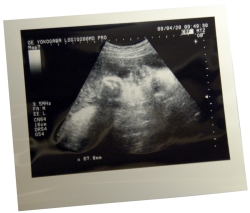

写真は、うちの娘ちゃん(臨月のころ)。当時は、元気に駆けまわっているいまの姿なんて、想像もつきませんでしたネ。しみじみ……。